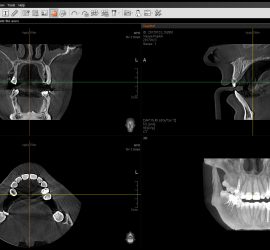

Учебный фильм по планированию имплантации в компьютерной программе EZ3D2009 (Vatech). Фильм по работе с EZ3D2009 можно посмотреть здесь.